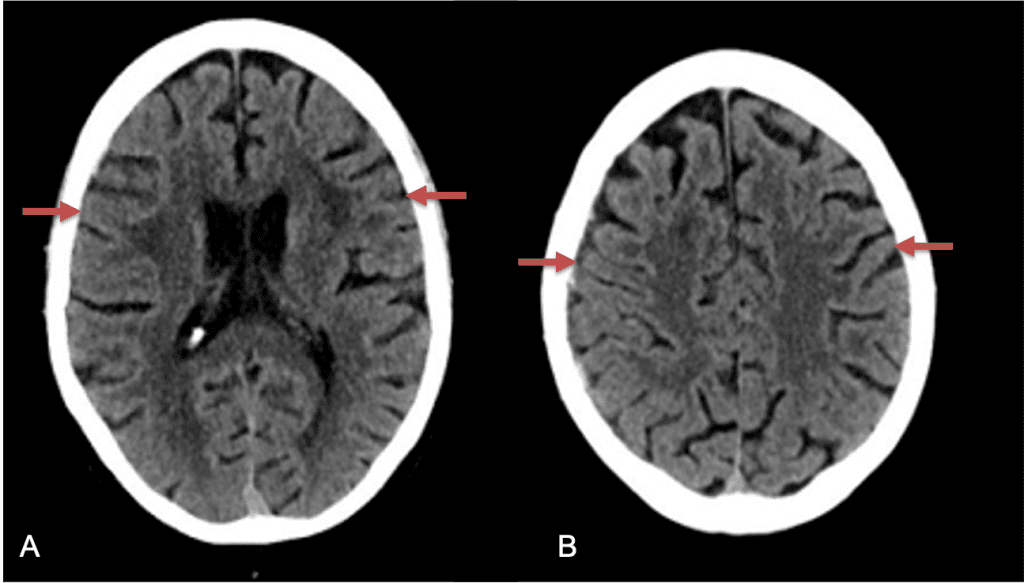

A woman in her 80s developed mild dizziness and headache following incidental trauma working in her garage one day. She presented several weeks later to the ER and was diagnosed with bilateral subdural hematomas, which were initially managed with observation, low dose Decadron, considering the mildness of symptoms, advanced age, and history of CLL with thrombocyptopenia (<100k). Over the next 4 weeks, the collections remained relatively stable with evidence of slight growth (10 to 12 mm thickness, and 2 mm right to left shift) on NCT (Figure 1. A and B).

Figure 1. A) 6 weeks post mild trauma B) 4 weeks post mild trauma demonstrates stable subacute subdural collections with mild growth and sulcal effacement.

CT follow-up at 1 week demonstrates early resorption. 2 weeks post MMA embolization, resolution of the left subdural collection with new small thin acute hemorrhage in an otherwise stable right subdural collection is observed (Figure 3. A and B).

Figure 3. A) 1 week post MMA embolization demonstrating decreasing thickness bilaterally B) 2 weeks post MMA demonstrates resolution on left, with small new acute component on right with overall decreased thickness.